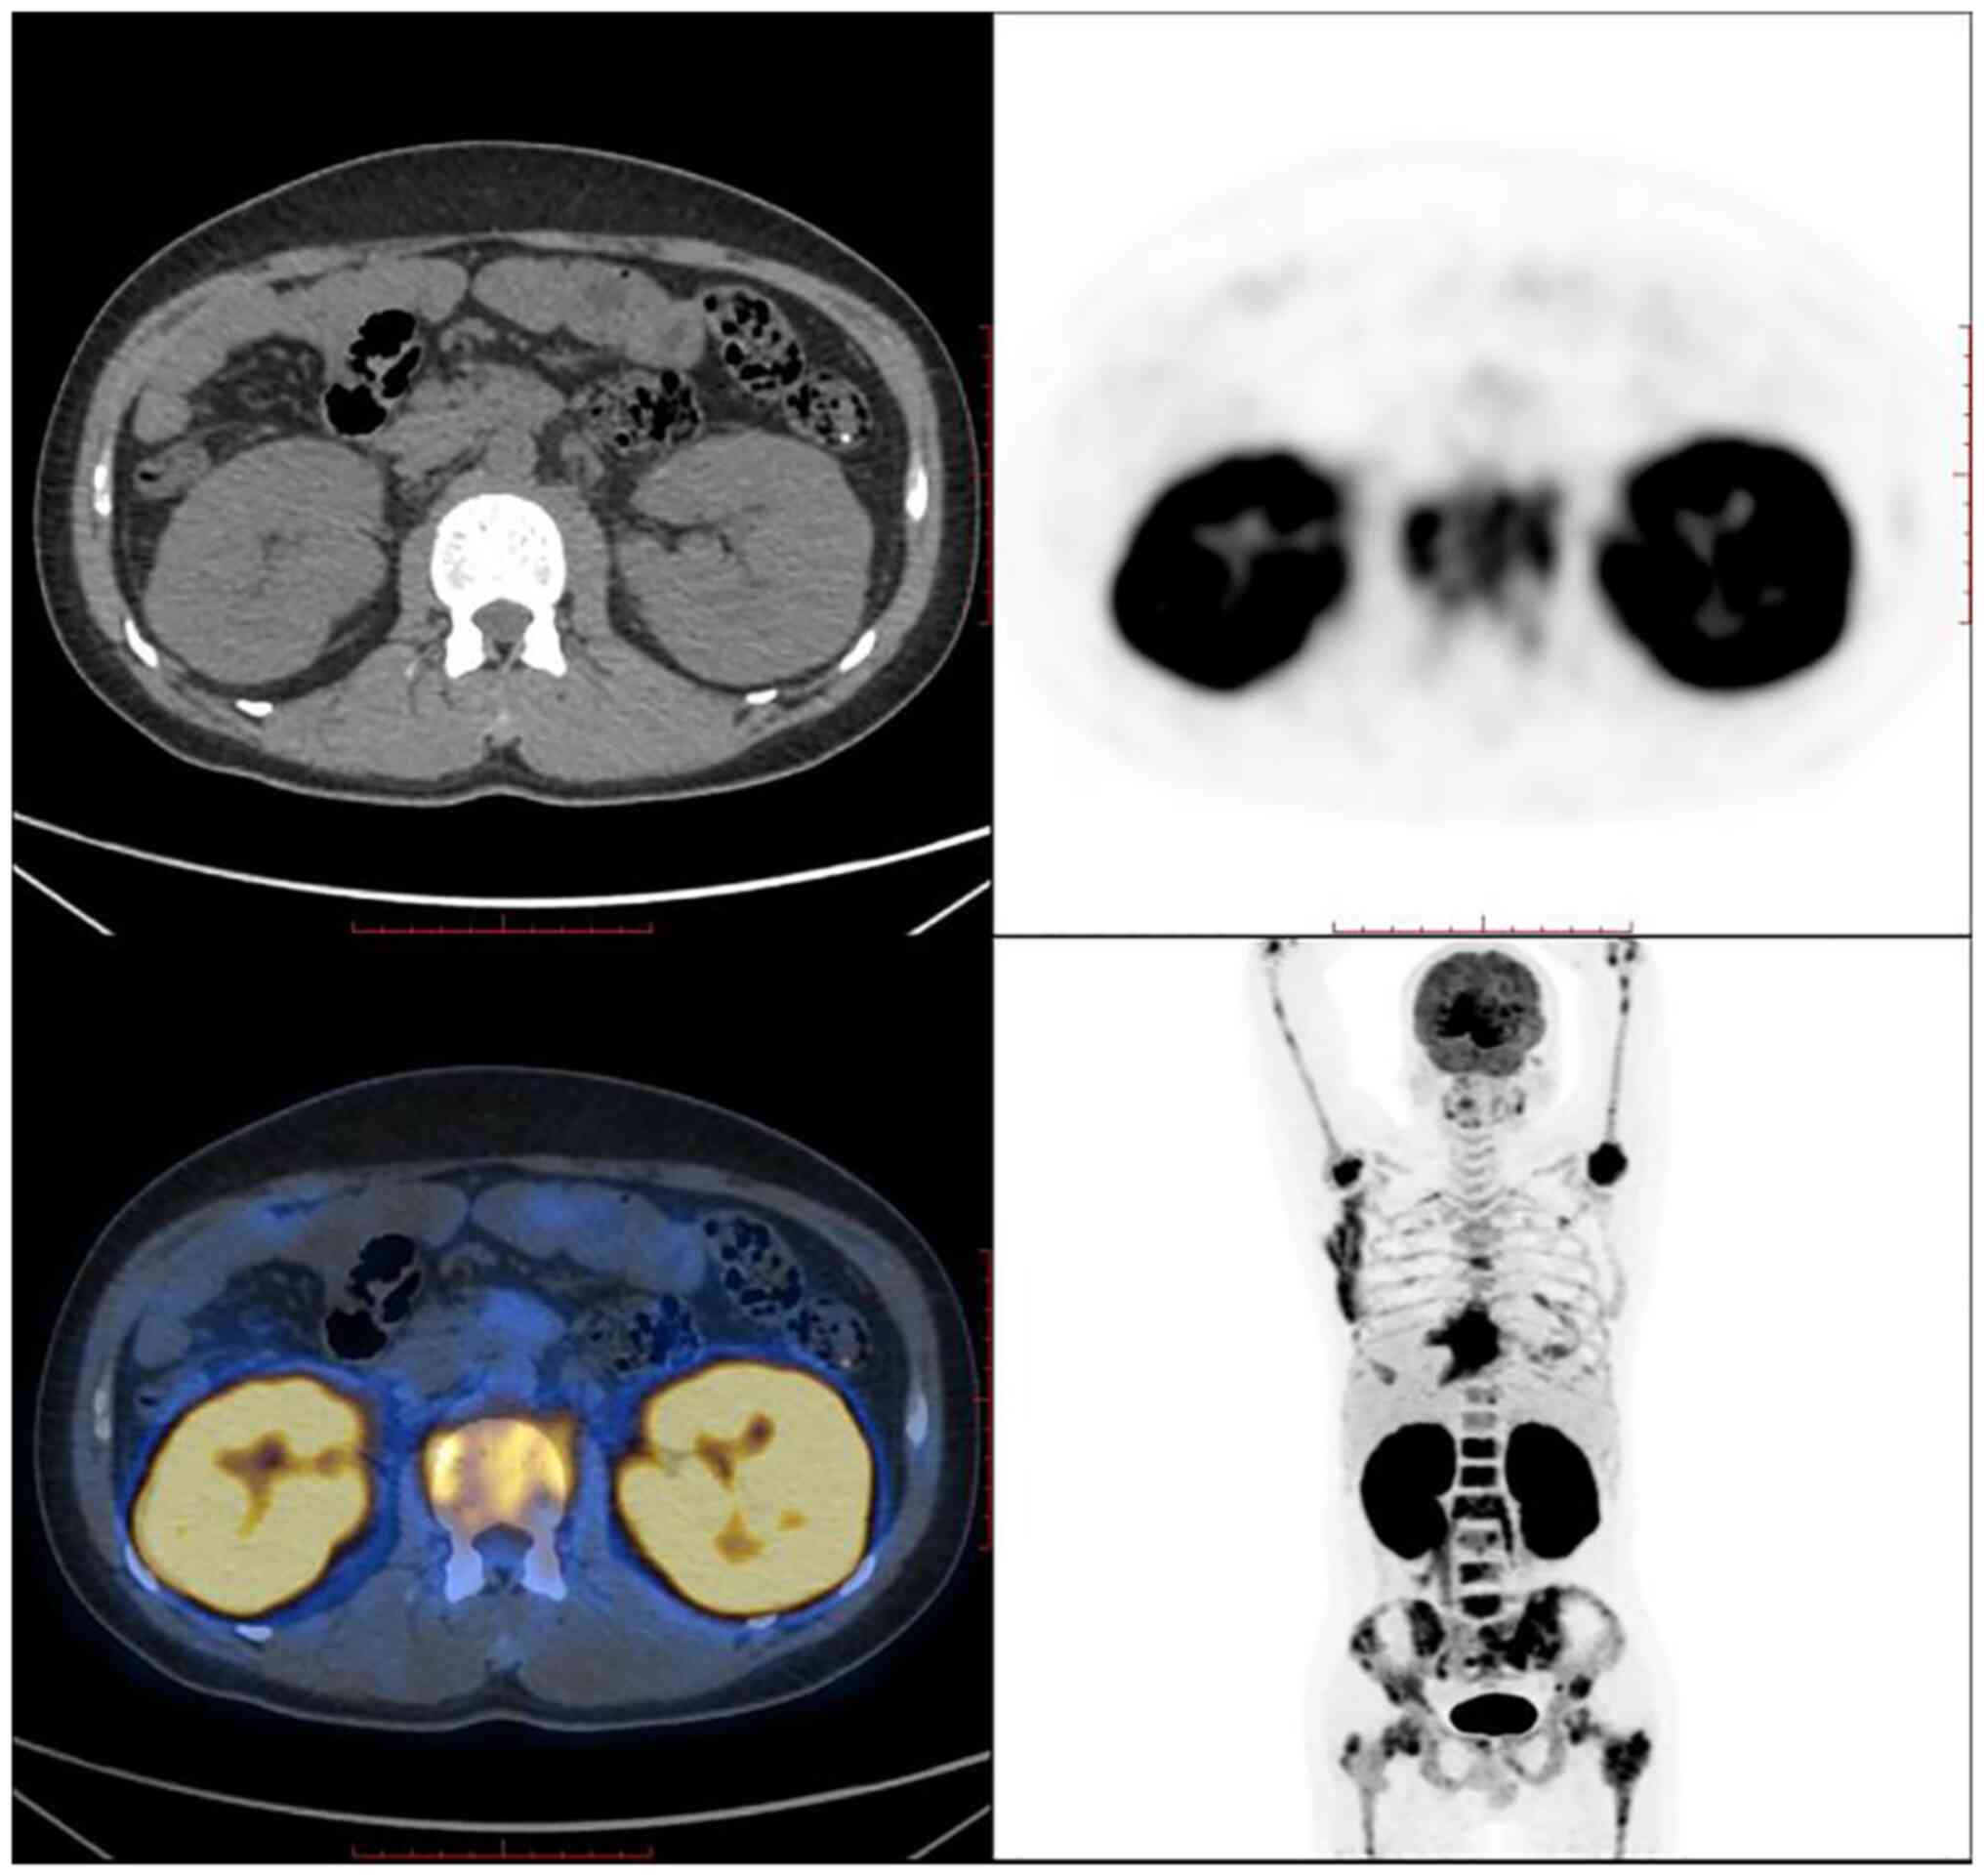

B‑cell lymphoblastic lymphoma‑associated renal damage: A case report and literature review

Lymphoblastic lymphoma (LBL) is a highly malignant form of lymphoma with rapid progression and high mortality. According to the World Health Organization immunophenotype, it is classified into T‑lymphoblastic lymphoma (T‑LBL) and B‑lymphoblastic lymphoma (B‑LBL). B‑LBL often involves lymph nodes and extranodal locations, such as the skin, bones, and soft tissues. However, renal damage as an initial symptom is very rare in B‑LBL. The present study presented a rare case of renal involvement in a 30‑year‑old male patient with B‑LBL presenting with acute renal failure with bilateral renal enlargement. Renal involvement is rare in B‑LBL, and nephrologists should improve the understanding of this disease.